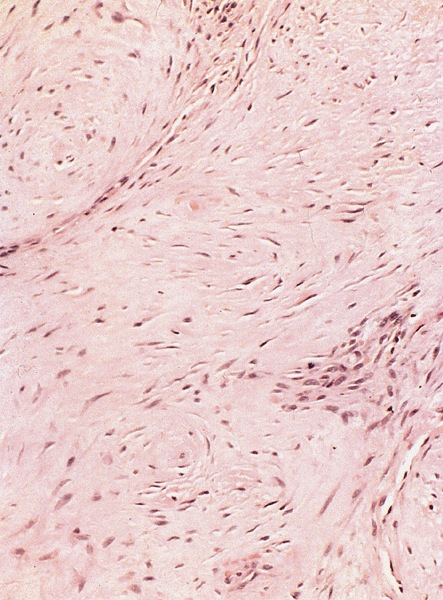

Microscopic (histologic) description

- Dense fibrous nodules, similar to those in Dupuytren contracture, fibromatosis and other desmoplastic conditions involving myofibroblasts

- More dense and less cellular than other types of superficial fibromatosis

- Disorganization of collagen of tunica albuginea with formation of nodules, often hyalinizing fibrosis

- Perivascular lymphoid infiltrate in early stages of disease in 1/3

- Fibrotic tunica albuginea with extension of fibrosis to corpus cavernosum

- Abnormal vessels with venous leakages

Positive stains

- Vimentin, variable actin - muscle specific and smooth muscle actin, less frequently desmin